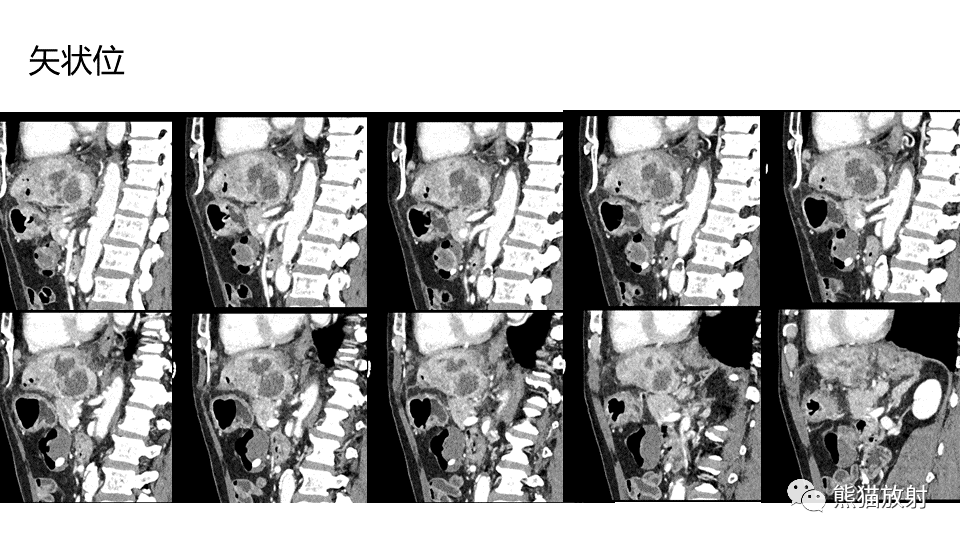

【PPT】肝内胆管细胞癌 VS 肝脓肿